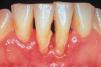

PeriimplantitisProceso inflamatorio destructivo (fig. 2) alrededor de un implante osteointegrado que conduce a la formación de una bolsa periimplante y a la destrucción del hueso circundante, desencadenado por la formación de biofilm en la superficie del implante. Ocurre en el 16% de los implantes y en el 26% de los pacientes. Cursa con dolor, inflamación y a veces supuración. Es muy característico el sangrado durante el sondaje realizado por el profesional para medir la profundidad de la bolsa periimplante. En la radiografía se aprecia pérdida ósea periimplante.